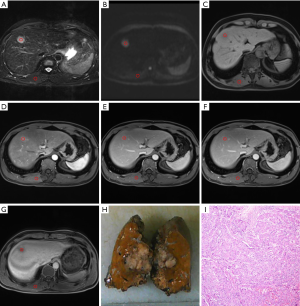

There was a statistically significant correlation between RCR and small HCC in arterial phase images (ρ=−0.305, P<0.05). In terms of multiple comparisons, the RCR of the small PD HCCs was significantly lower than that of the small WD HCCs (P<0.05), whereas no significant difference existed between small WD HCCs and MD HCCs (P=0.083) (Figures 3,4), or between small MD HCCs and PD HCCs (P=0.076).

This study demonstrated that the correlation between RCR and small HCC in arterial phase images is statistically significant. There was a significant difference in the RCR between well- and PD HCCs, though not among other histological grade combinations. In previous studies regarding intravoxel incoherent motion, the perfusion fraction has been shown to be positively correlated with the contrast agent enhancement ratio in the arterial phase (30). In our study, the mean arterial phase RCR of WD HCCs tended to be higher than that of other histological grades.